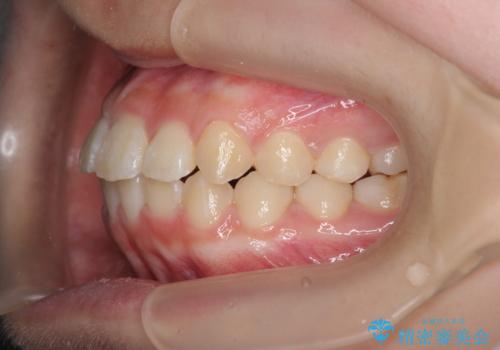

インビザラインで行う八重歯の治療

- 笑った時に目立つ八重歯の矯正治療を求めて来院されました。

マイクロインプラントを用いた臼歯の後方牽引、およびゴムかけ等の付加処置を駆使して八重歯の治療を行っていきます。

しっかりとゴムかけを頑張っていただいたおかげで、上顎臼歯の後方移動が達成されしっかりとした噛み合わせの構築と、八重歯の治療を達成することができました。